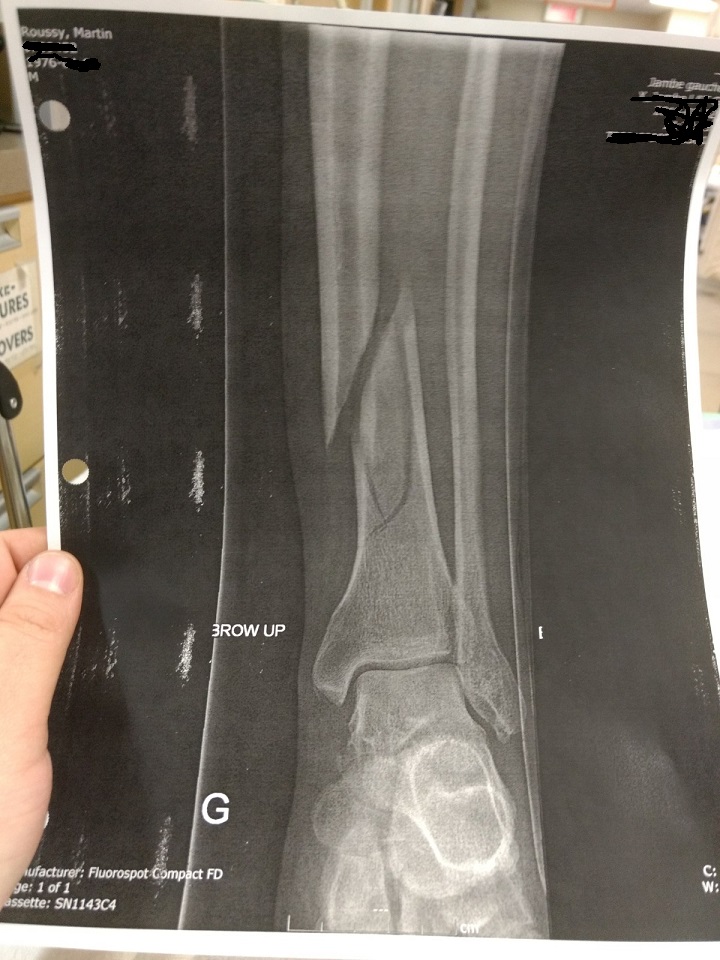

Du Bon Manger – Tibia Published 19 Mai 2018 at 720 × 960 in Du Bon Manger – Du manger d’hôpital et autres gourmandises… Partager : Partager sur Facebook(ouvre dans une nouvelle fenêtre) Facebook Partager sur X(ouvre dans une nouvelle fenêtre) X J’aime chargement…